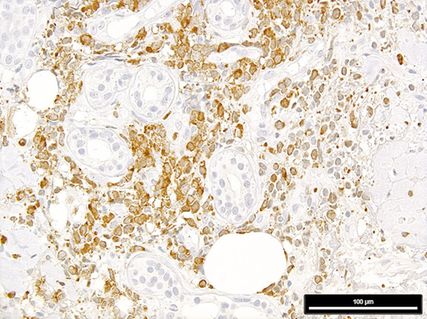

Abb. 2: Expression von mutiertem NPM1 in einer Leukaemia cutis (man beachte die negativen, da nichtmutierten, Hautadnexe); Immunperoxidase-Färbung mit dem mutationsspezifischen Antikörper PA1-46356

In einem letzten Schritt ist eine ICC2022/WHO-5-Diagnose zu stellen.11,12 Dafür sind zusätzliche Färbungen für p53 (eine starke diffuse Färbung indiziert eine AML/MN mit mutiertem TP53) und für NPM1 mit einem mutationsspezifischen Antikörper13 (eine zytoplasmabetonte Färbung indiziert eine AML/MN mit mutiertem NPM1; Abb. 2) sowie Analysen mit ausgewählten FISH-Sonden und NGS-Panels für subentitätsbestimmende genetische Aberrationen nötig.